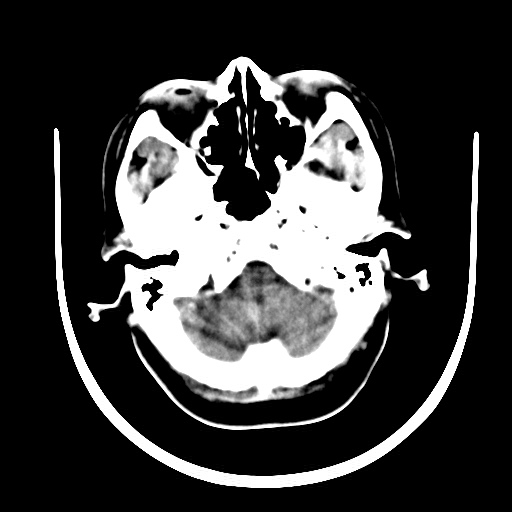

标题: CT16579:女 65岁间断性抽搐. [打印本页]

标题: CT16579:女 65岁间断性抽搐.

考虑右侧颞叶脑软化灶并脑穿通畸形;建议必要时行进一步检查。

右侧蛛网膜囊肿

右颞叶脑软化灶。余未见明显异常。

考虑右颞叶脑软化灶

右颞叶软化灶,右基底节区腔隙性脑梗塞;